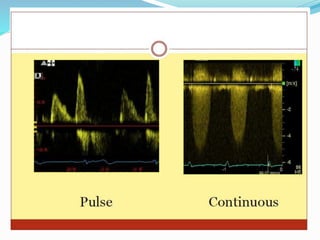

Continuous wave (CW) Doppler

Pulsed wave (PW) Doppler

3. Doppler echocardiography

49

Doppler echocardiography is a method for

detecting the direction and velocity of

moving blood within the heart.

Pulsed Wave (PW) useful for low velocity

flow e.g. MV flow

Continuous Wave (CW) useful for high

velocity flow e.g aortic stenosis

Color Flow (CF) Different colors are used

to designate the direction of blood flow.

red is flow toward, and blue is flow away

from the transducer with turbulent flow

shown as a mosaic pattern.